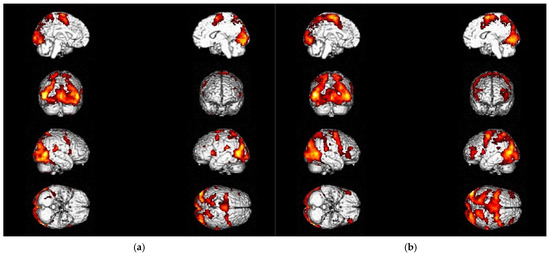

3.3. Differences in Activation Due to Treatment Methods